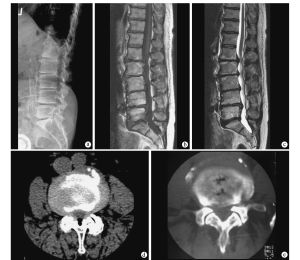

3、如果病人因腰部疼痛而就診,常規的X線檢查是必要的。如果存在椎間盤退行性變,X線就會顯示椎間隙變狹,這就表示有椎間盤萎縮或破裂。骨質增生多發生在椎體和小關節的邊緣。X線可以顯示出這種叫骨贅的增生物。椎間盤破裂和骨贅的形成導致容納神經根的空間變小。神經根通過叫做神經孔的骨性通道穿出椎管,這些通道特別容易發生狹窄。

4、大多數情況下,醫生們會通過MRI或CT來幫助診斷腰椎間盤退行性變。MRI能很清楚地顯示椎間盤突出和神經根受壓的位置。CT通常被用來顯示脊柱的骨骼解剖結構,所以能顯示神經根在神經孔和椎管內剩餘空間